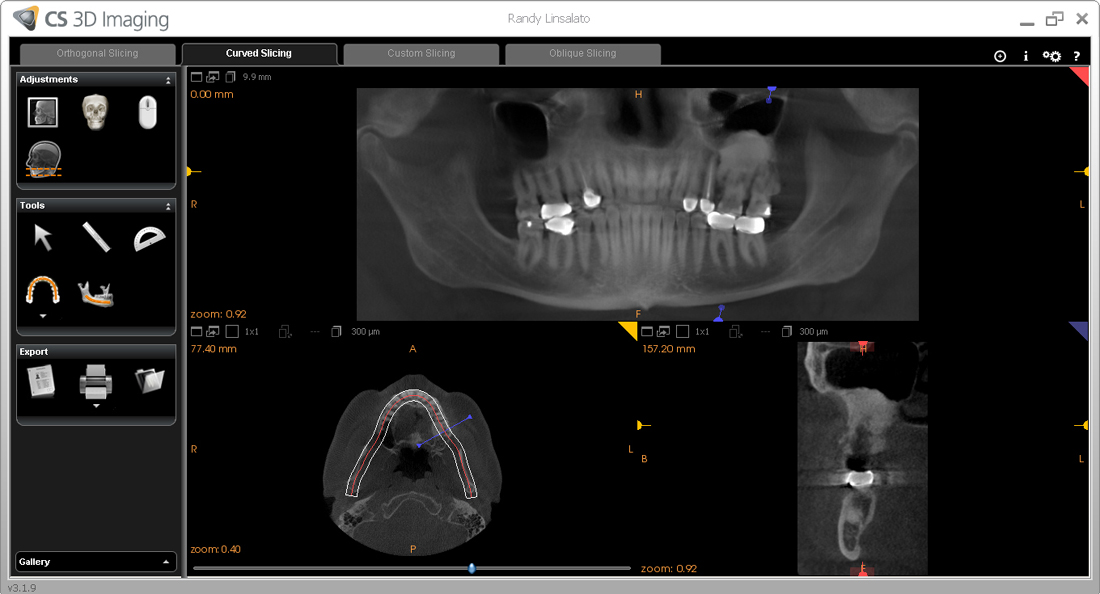

He took the scan below to see the extent of the Osteoma.

As you can see the dense bone mass extends from my lower sinus down around the roots my teeth 14 and 15

Involvement of teeth 13,14, and 15 is obvious.